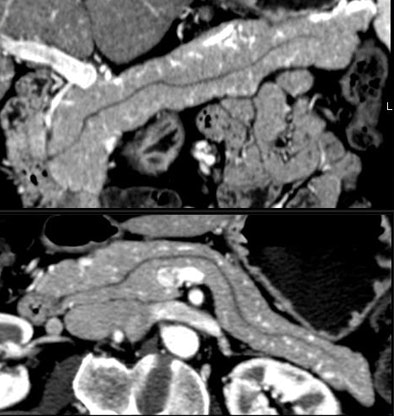

Certainly imaging-based diagnosis of the cysts has its limitations. For one thing, MDCT can diagnose six different pancreatic lesion types, including side branch intraductal papillary mucinous neoplasms (IPMNs), serous microcystic adenomas, epithelial cysts, mucinous cystic neoplasms, lymphatic cysts, and cystic islet cell tumors. But it can't always tell them apart.

Worrisome features for malignancy are solid tissue within the cyst, obstruction of the main pancreatic duct ≥ 1 cm or the common bile duct, regional lymphadenopathy, or interval enlargement of a lesion, Jeffrey said.

In their series, Lee et al also reported the radiographic features correlating to malignancy as presence of a solid component (p < 0.0001), main pancreatic duct dilation (p = 0.002), common bile duct dilation (p < 0.001), and lymphadenopathy (p < 0.002).

"The presence of solid tissue within cystic lesions in addition to regional lymphadenopathy and interval enlargement are all very significant features suggesting malignancy," Jeffrey said.

Small cystic lesions not worrisome for malignancy under 3 cm include side branch IPMNs, and serous microcystic adenomas, which are easily characterized by their honeycomb matrix that is also easily seen on ultrasound, Jeffrey said.

Serous cystic tumors are by far the most common pancreatic cystic lesions, Jeffrey said. They are nearly always microcystic, with macrocystic serous lesions occurring in about 4% of cases. They also are benign and can be managed with follow-up but not surgery, he said.